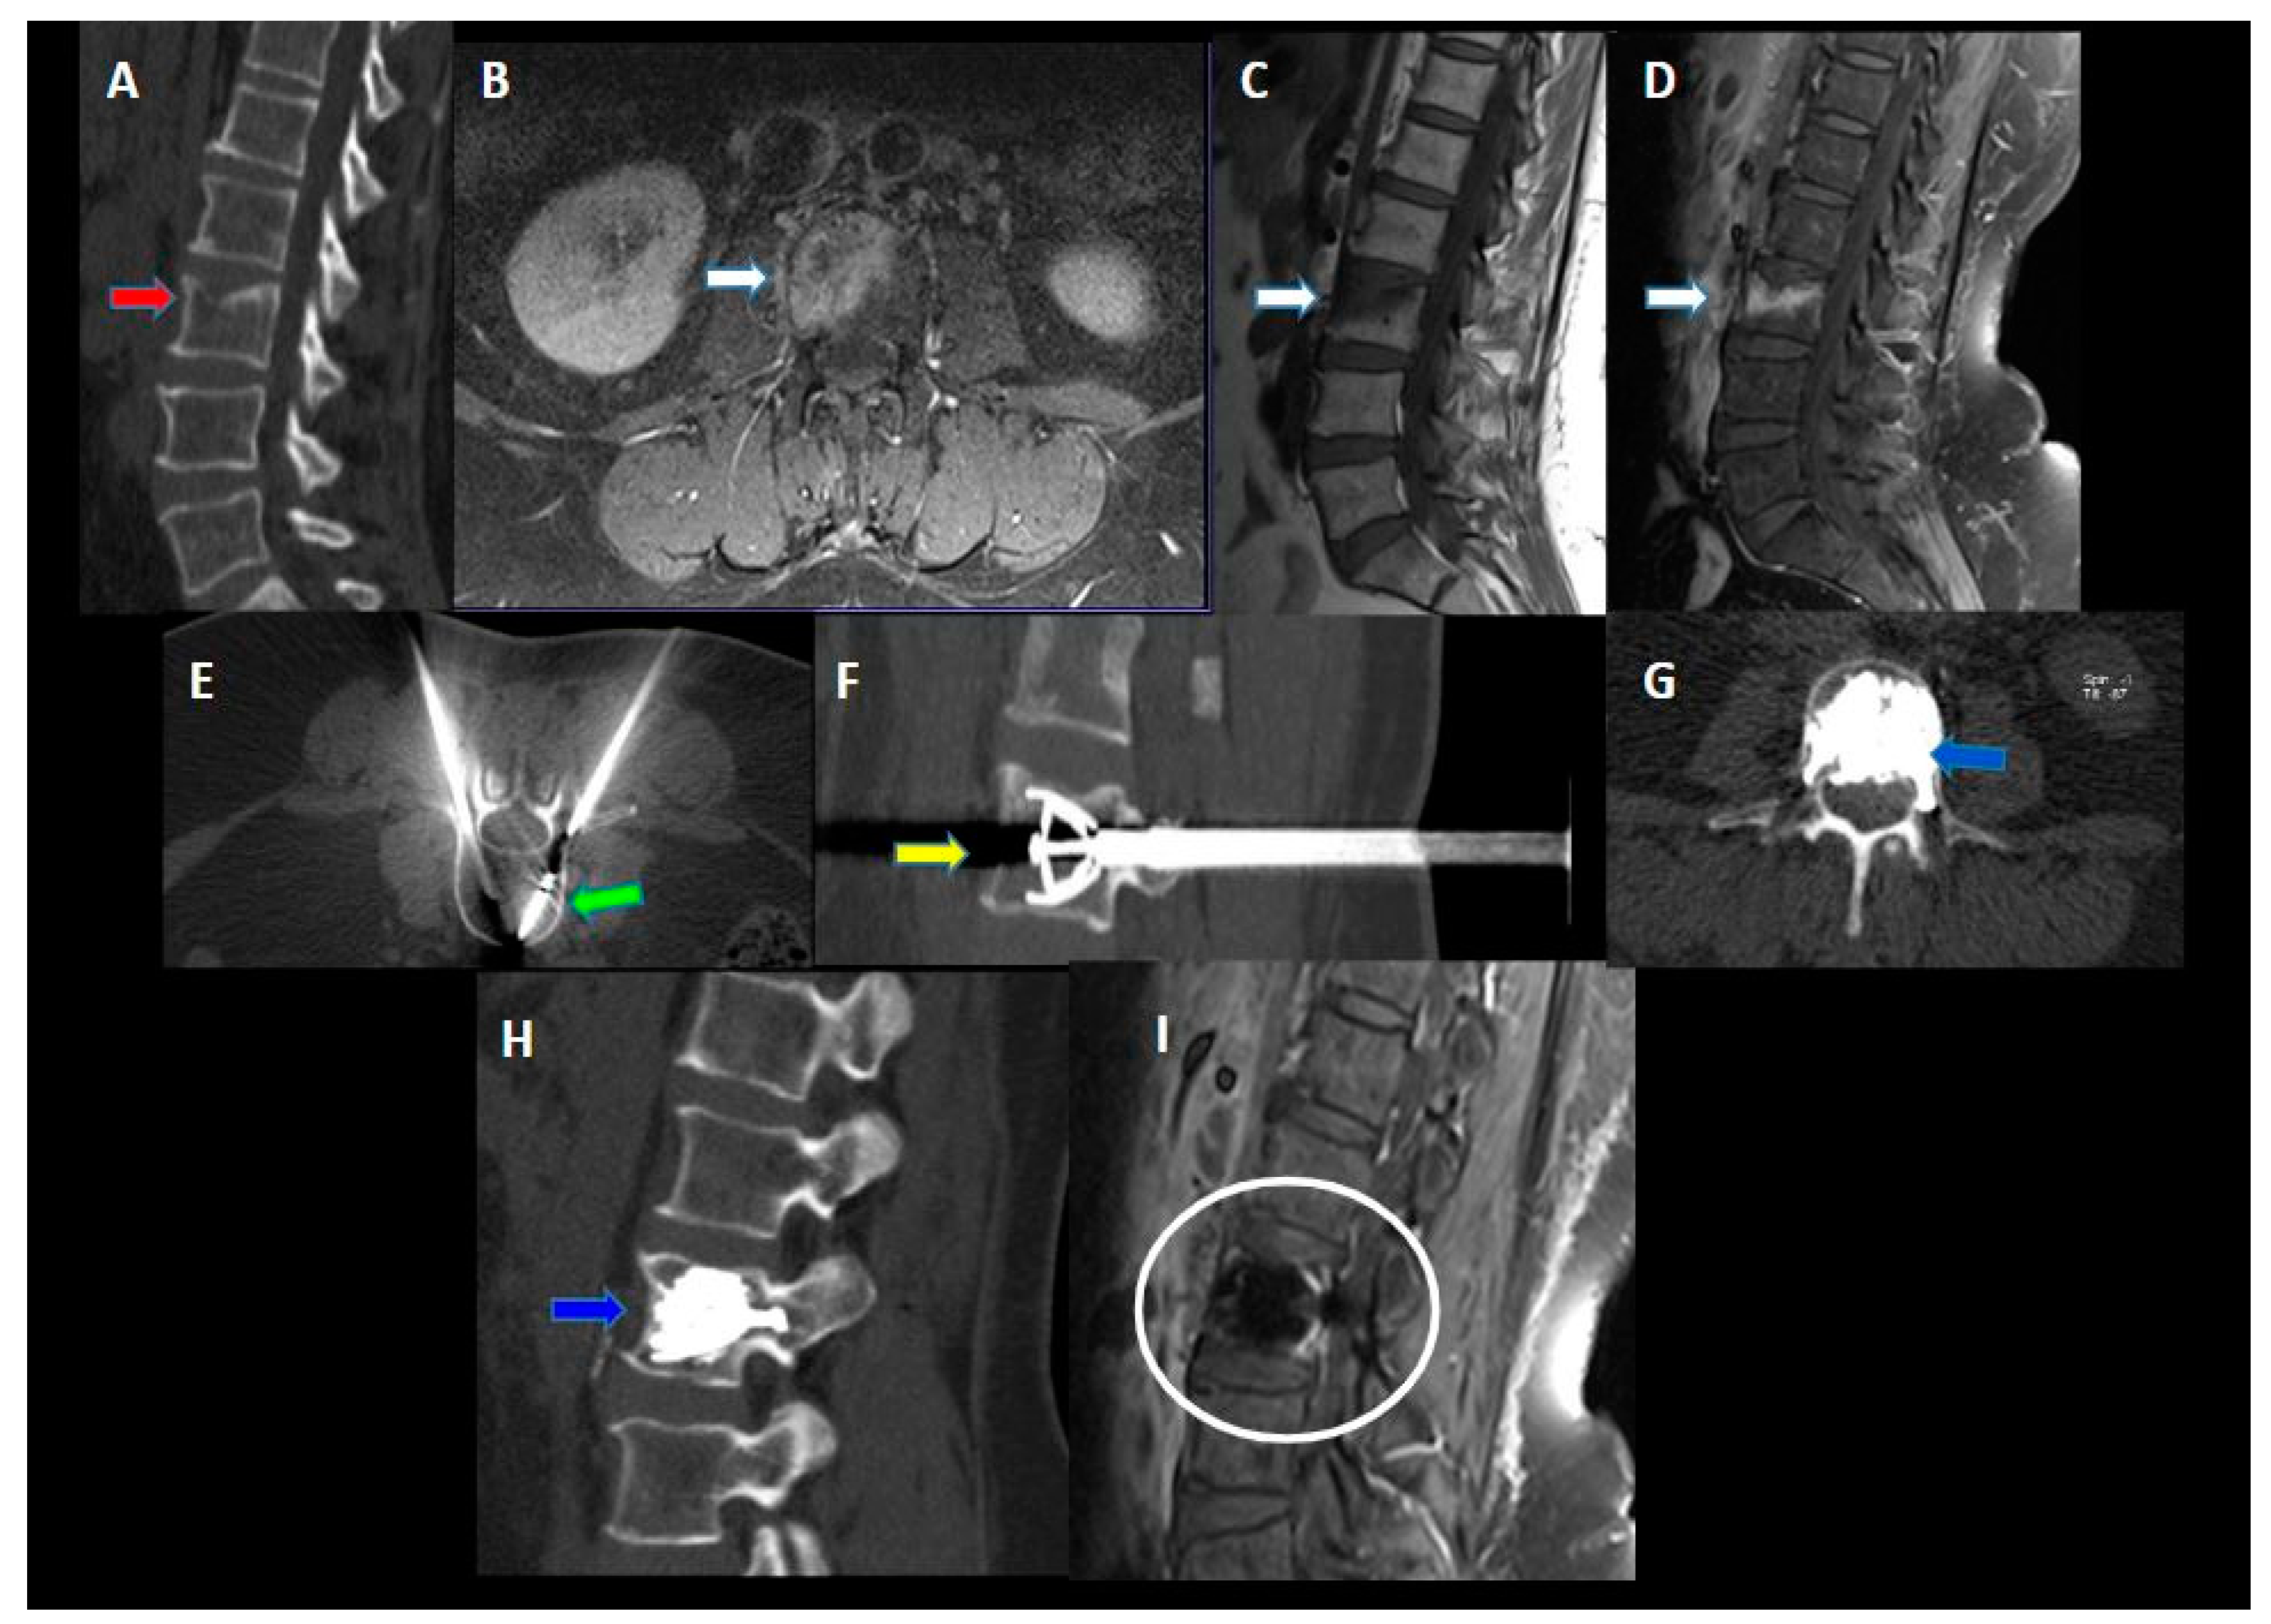

2. Materials and Methods